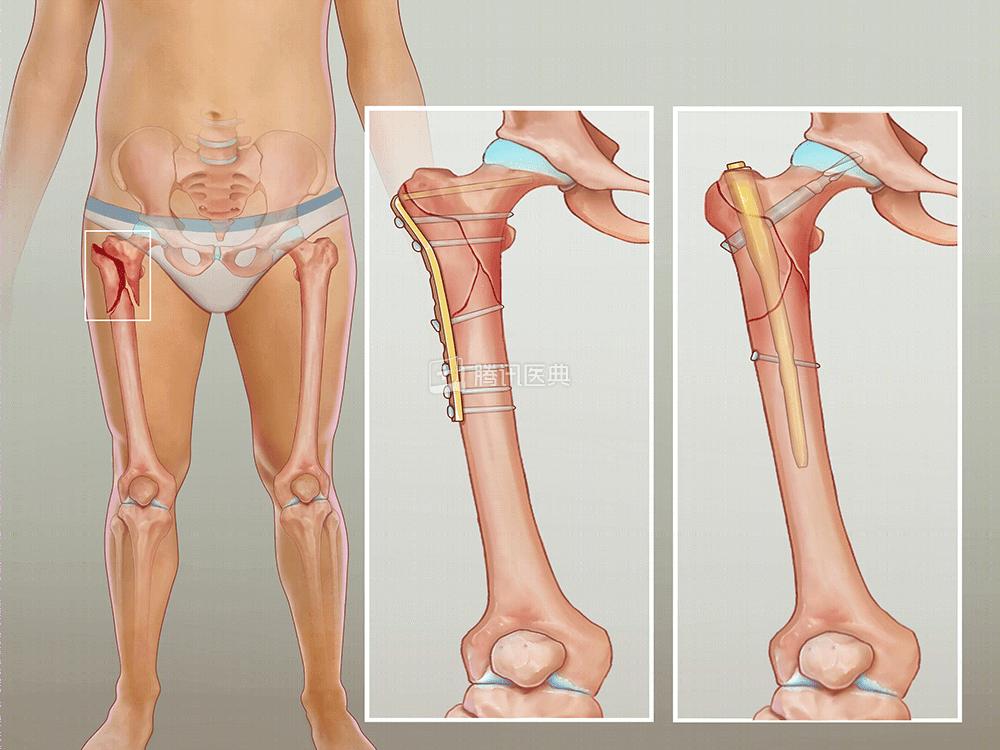

(动脉瘤样骨囊肿示意图。医典自制)这个病最常发生在10~20岁的儿童青少年,30岁以上就非常少见了。它最常发生在长管状骨的头端、脊柱和骨盆[2]。

什么叫长管状骨呢?

其实就是“大腿骨”(股骨)、“小腿骨”(小腿的胫骨和腓骨)等长长的那些骨头。